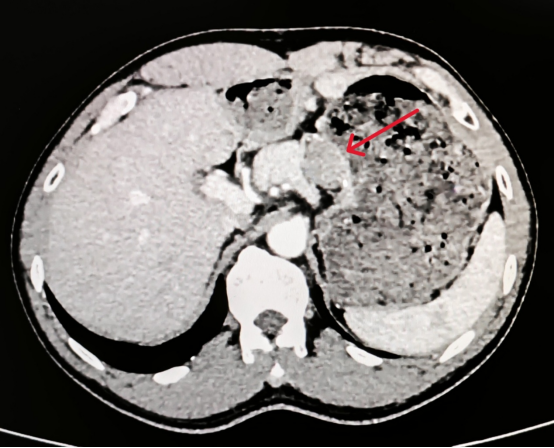

术前腹部增强CT发现复发的胃间质瘤(红色箭头所示)